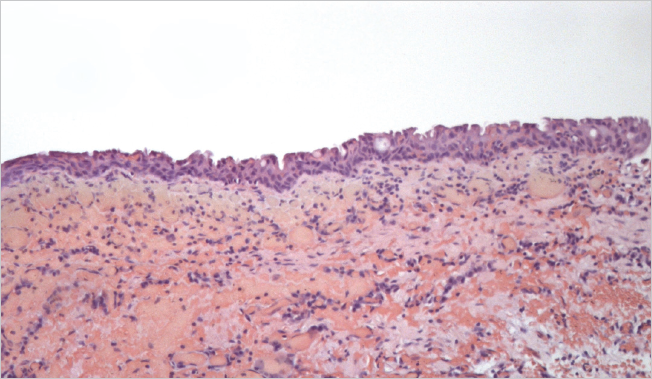

Histological examination of the removed paraurethral cyst was performed (Fig. 6–8).

Fig. 7.The wall of the paraurethral cyst, surgical material. Hematoxylin-eosin staining, ×100. Epithelium with signs of dystrophia and minimal desquamation are represented

Рис. 7.Стенка парауретральной кисты, операционный материал. Окраска гематоксилином и эозином, ×100. Эпителий с признаками дистрофии и минимальной десквамации

Fig. 8.The wall of the paraurethral cyst, surgical material. Hematoxylin-eosin staining, ×100. Foci of epithelial lining atrophy are determined

Рис. 8.Стенка парауретральной кисты, операционный материал. Окраска гематоксилином и эозином, ×100. Определяются очаги атрофии эпителиальной выстилки